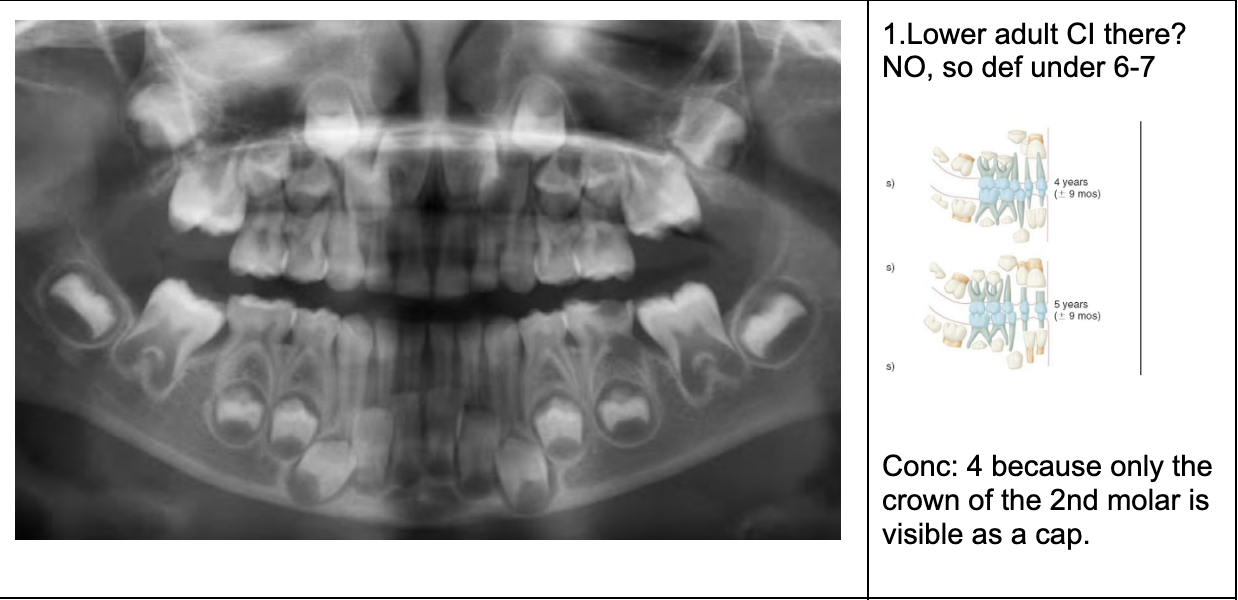

Permanent lower incisors present? Yes, so definitely 6-7

Permanent upper Incisors not erupted yet. Therefore not 7-8 y.o.

Conclusion = 6 y.o